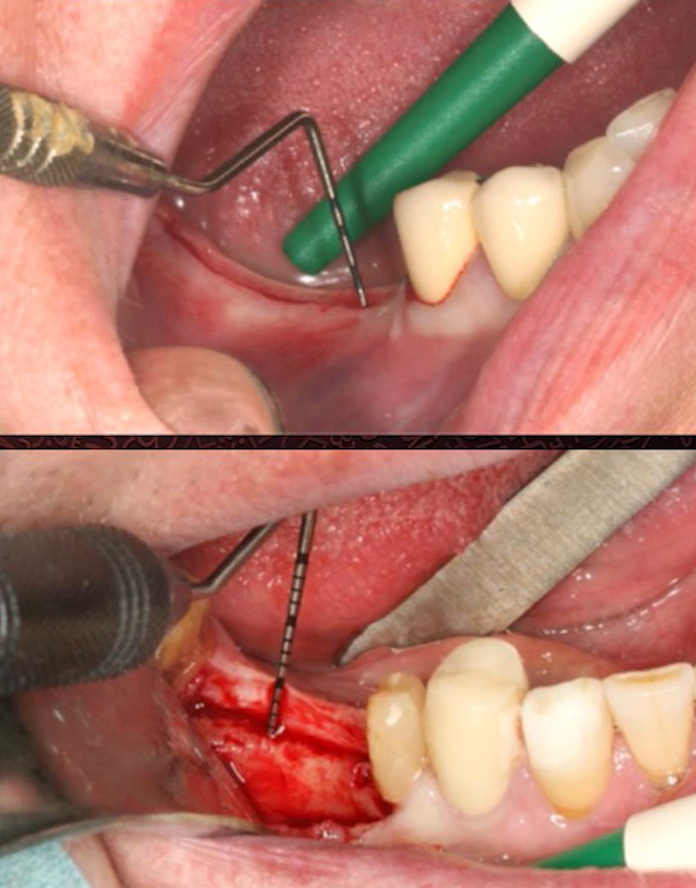

Volunteers had two identical implants placed side by side and, if possible, at the same level relative to the bone. The only difference was that one had a platform switch, while the other did not (see photo below).

Implant placement without platform switching (left) and with platform switching (right) – the goal is to determine the difference in marginal bone loss. YouTube/ Implantarium/ Rauf Aliyev

The initial gingival height was measured during the soft tissue dissection stage. The difference is visible in the image below. The top slide shows very thin gingiva, while the bottom slide shows much thicker gingiva.

The group with thin gingiva included patients whose soft tissue thickness was 2 mm or less, and the group with thick gingiva included patients whose thickness was more than 2 mm.

Measurements of the thickness of the gingiva above the alveolar ridge: upper image – thickness <2 mm; lower image – thickness >3 mm (almost 5 mm). YouTube/ Implantarium/ Rauf Aliyev